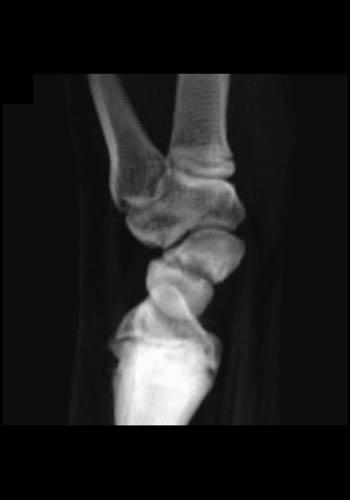

Indications for CT include high clinical suspicion with a negative radiograph, equivocal radiograph findings, comprehensive evaluation for angulation and displacement in the setting of a fracture, follow up assessment for healing and union, as well as post-operative imaging. The conventional radiograph can not always provide a complete evaluation due to obscuration of the scaphoid by the other carpal bones. Furthermore, if the radiograph demonstrates excessive dorsal tilt of the lunate, CT is required to exclude displacement of a scaphoid waist fracture. Dorsal tilt can be secondary to scaphoid waist fracture displacement as well as intercarpal ligament injury. Furthermore, the presence of dorsal tilt of the lunate has been shown to correlate with malunion and nonunion in 83% of cases. An additional radiographic finding which would prompt further evaluation with CT is the presence of scaphoid lucencies. In a small percentage of scaphoid fractures (.3%), lucencies within the scaphoid bone were detected with no fracture line apparent on the radiograph. On CT, a fracture line was evident. These pseudocysts are hypothesized to arise secondary to ischemia, and indicate nonunion of scaphoid microfractures.

Malunion can manifest as a “dorsal humpback deformity”. This finding is not always apparent on conventional radiographs due to obscuration by overlying bones. Owing to palmar angulation of the distal fracture fragment, the dorsal surface of the bone develops a bony prominence. Complications of this deformity include radiocarpal osteoarthritis and functional impairment.

Nonunion has been reported in 5% of treated scaphoid fractures and in 33-55% of unstable fractures. Determination of whether a scaphoid fracture has united is better served by CT than radiographs. CT is more sensitive for detecting bone bridging and for identifying focal regions of nonunion within proliferative bone. Nonunited scaphoid fractures have been classified by the type of displacement (volar vs. dorsal), which has been shown to correlate with the fracture location (proximal vs. distal to the dorsal apex of the ridge of the scaphoid). Volar displacement is present when the distal fragment overlaps the proximal fragment volarly, and dorsal displacement when the overlap occurs dorsally. CT with 3D reconstructions was performed on nonunited scaphoid fractures and the fracture location was shown to correlate with the type of displacement. Distal fractures were associated with volar type nonunion, and this type of nonunion had a 100% incidence of DISI. Dorsal type nonunions were associated with proximal fractures, and only 30% developed DISI. In addition, the 3D renderings were used for proximity mapping of the distances between the bones. The results showed a change in the radiocarpal contact areas in association with dorsal type displacement.